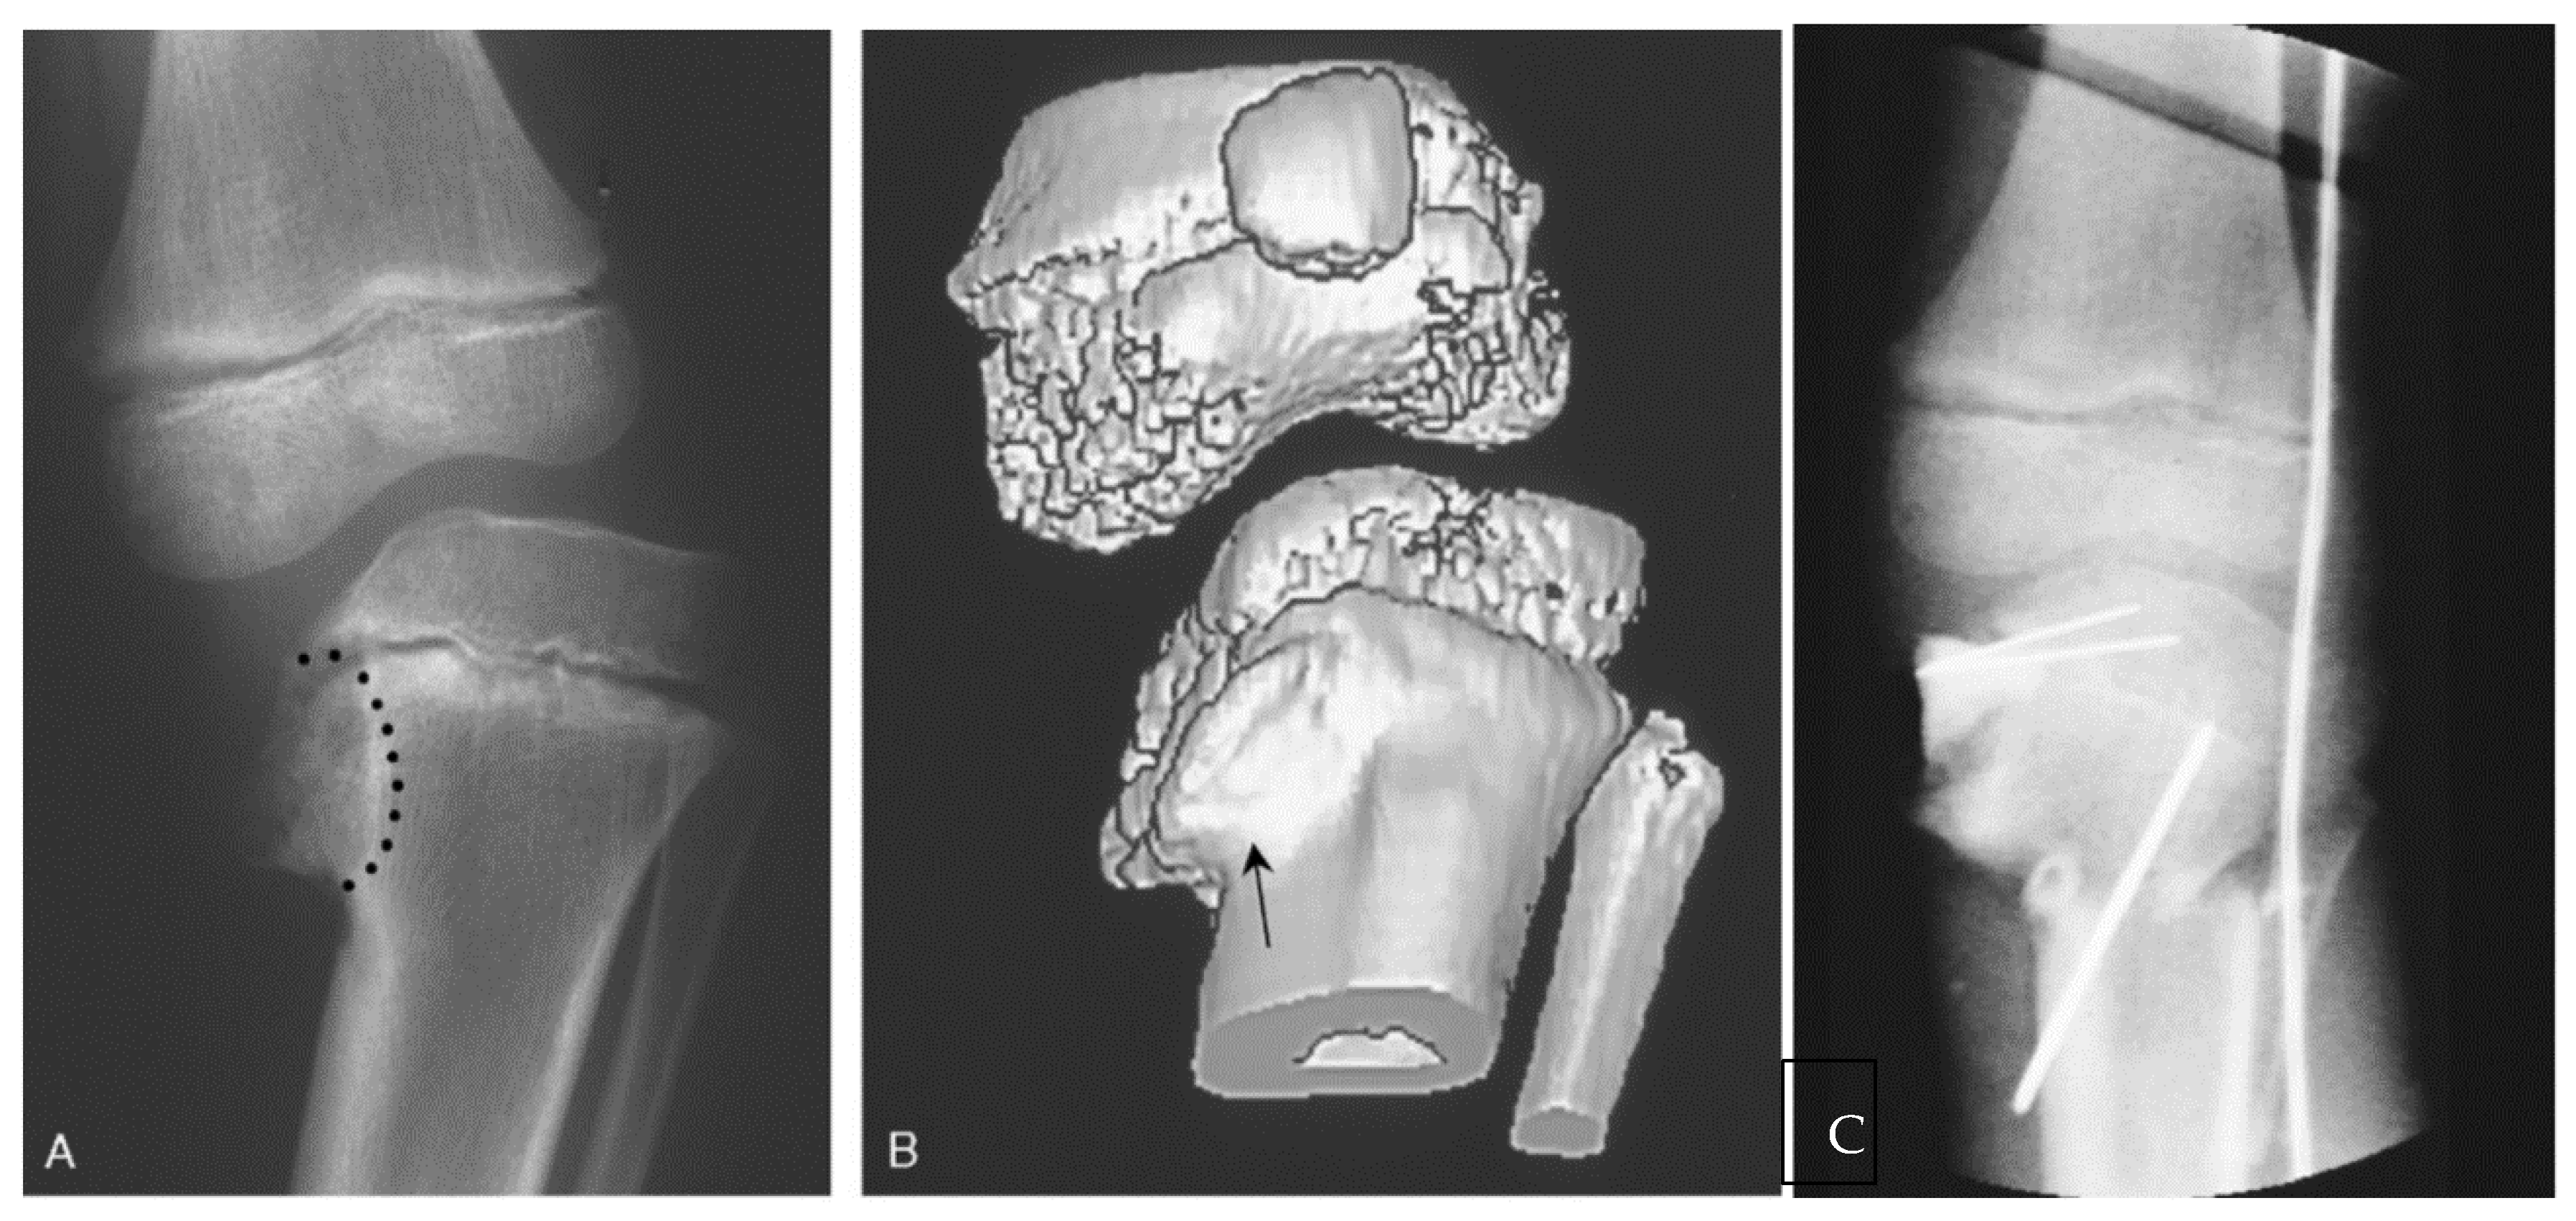

13. Osteotomies with Acute Correction

14. Hemi-Plateau Elevation Osteotomy